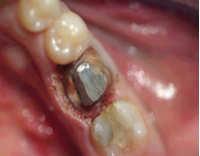

At this treatment and setting, one work with Anestesie. The anaemic working, allow us a very good view to be able to prepare a perfect tooth stump.

In one single treatment, the gingivectomy can done and the tooth stump is prepared.